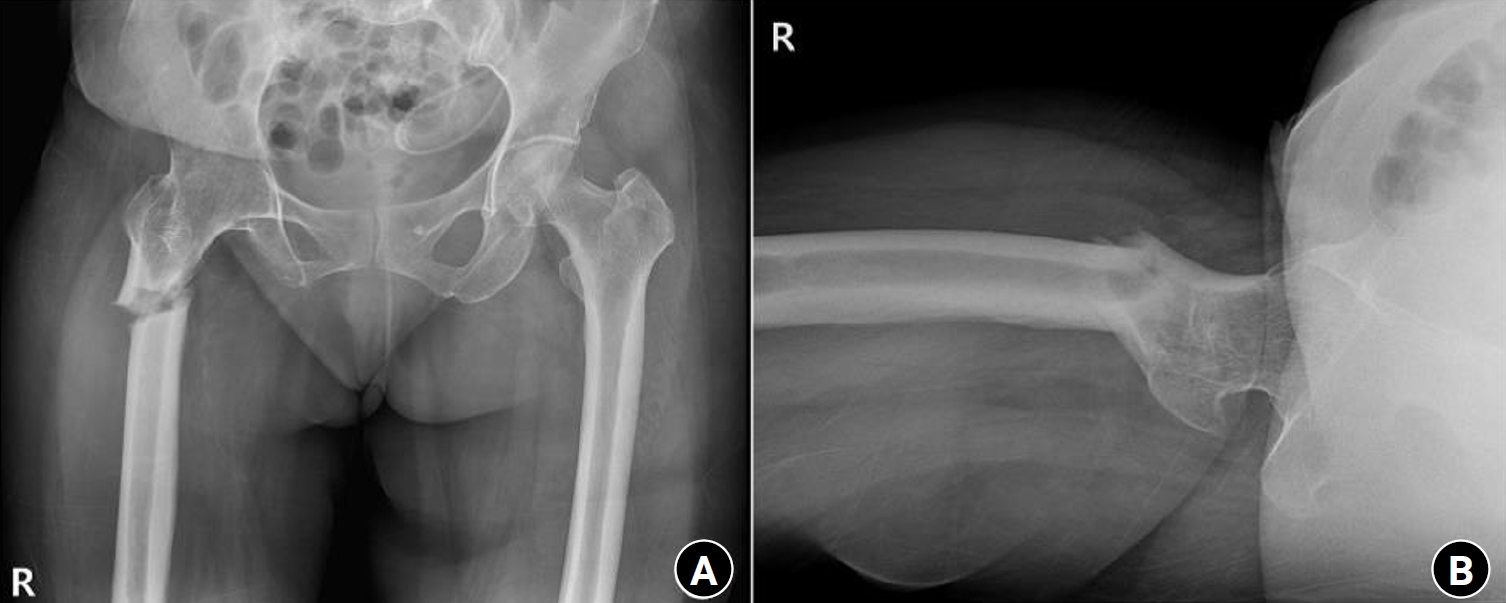

Previous studies have extensively examined the association between femoral insufficiency fractures and prolonged bisphosphonate therapy. However, alternative etiologies remain insufficiently characterized. This study aimed to analyze non-pharmacologic factors associated with femoral insufficiency fractures, with particular emphasis on paradoxical cortical hypertrophy and altered biomechanical load distribution. We reviewed three cases of femoral insufficiency fracture that were surgically treated at our institution between January 2018 and January 2022. None of the patients had a history of bisphosphonate use. Clinical histories—including underlying comorbidities, prior surgical procedures, and radiographic findings—were evaluated. Serial radiographs obtained before and after fracture occurrence were analyzed to characterize fracture morphology and associated cortical changes. Case 1 involved a patient with post-traumatic hip synostosis; case 2 involved a patient with osteogenesis imperfecta; and case 3 involved a patient who had previously undergone intramedullary nailing for an intertrochanteric fracture. Lateral femoral bowing and cortical hypertrophy preceded fracture development in two cases, whereas focal cortical hypertrophy at the distal locking screw site was observed in the third case. No history of bisphosphonate therapy was identified in any patient. Fractures developed at sites characterized by increased cortical remodeling and abnormal load concentration. Femoral insufficiency fractures can occur in the absence of bisphosphonate therapy. Paradoxical cortical hypertrophy and altered biomechanical force distribution appear to be important contributing factors. Level of evidence: IV.